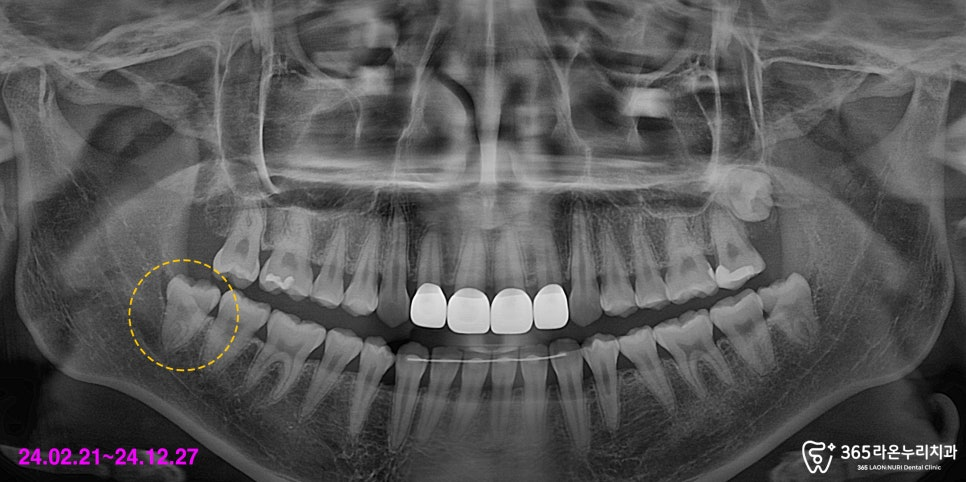

그래서 3차원 정밀을 촬영하여

사랑니 및 하치조 신경의 위치 파악 및

발치 계획을 세웠는데요.

그리고 나서, CT 사진을 보시면

사랑니 뿌리 끝과 하치조 신경이

닿아 있는 것을 확인할 수 있습니다.

이렇게 치아 뿌리와 긴밀하게 닿아 있다면

주변 구조물에 손상을 일으키지 않게 뽑아야 되므로

그만큼 사랑니 발치가 까다로워집니다.